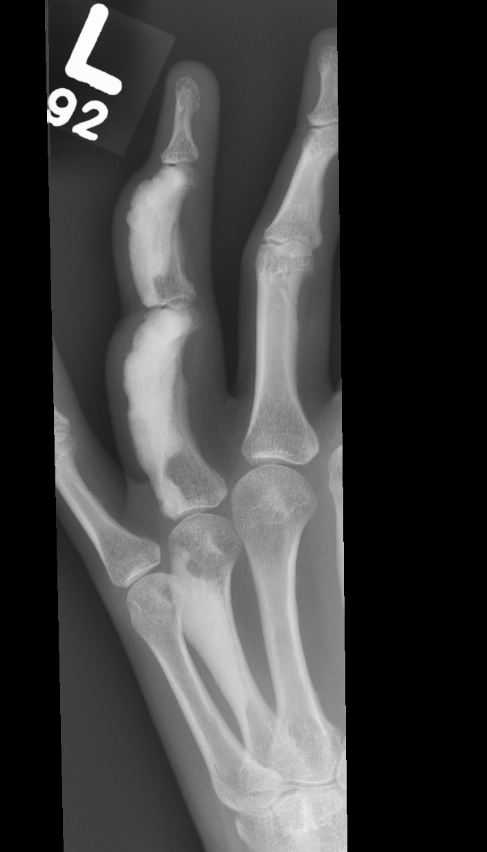

X-ray

Sclerotic lesions of bones

- undulating cortical hyperostosis

- look like wax dripping down the side of a candle